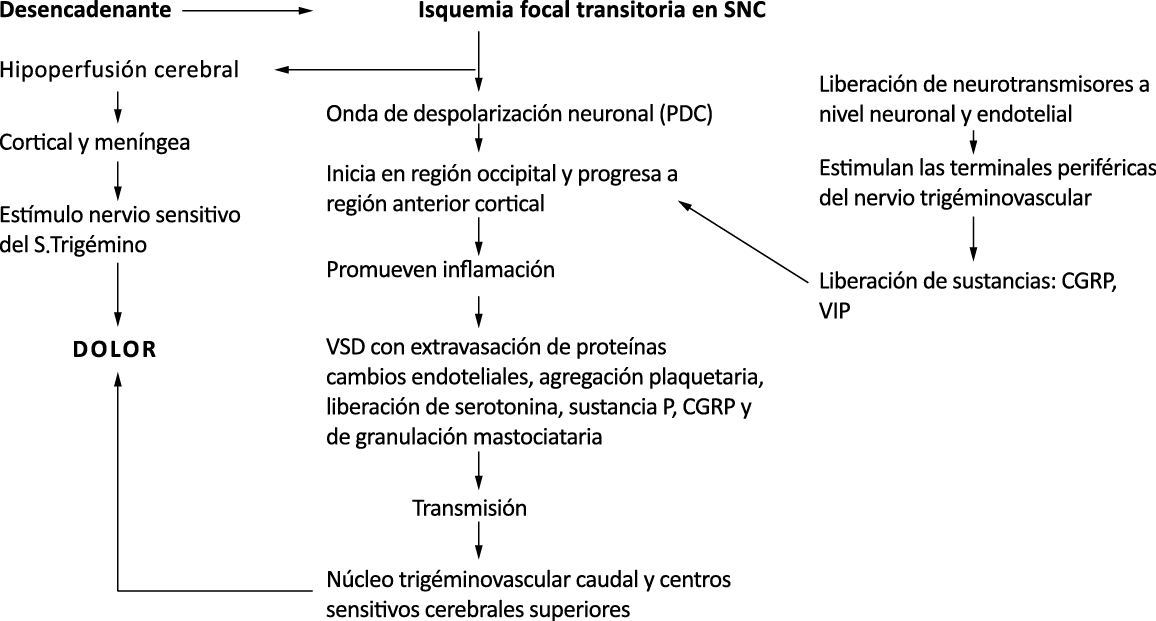

El aura de la migraña, al menos en su sentido clásico, tiene relación con la depresión cortical que se propaga por la corteza cerebral y participa como un actor paralelo cuando se producen las crisis. (Figura 2)

Se cree que una onda transitoria de despolarización neuronal de la corteza (Figura 9), la depresión de propagación cortical (CSD), es el mecanismo cerebral fisiopatológico subyacente al fenómeno clínico del aura de la migraña. Leão(21) estableció un mecanismo subyacente hipotético. Luego de haber estimulado eléctricamente la corteza de conejo y encontrar una depresión EEG que se propagaba a una velocidad similar de 3 mm/min centrífugamente desde el sitio de estimulación sugirió que podría ser la base del aura migrañosa. Esta hipótesis está fundamentada en la correlación entre las características neurofisiológicas de una CSD, su propagación retinotópica en la corteza visual y las características y dinámicas de los déficits visuales(14, 15) y en las observaciones indirectas derivadas de los estudios de imágenes que respaldan aún más este concepto(16) Sin embargo, sobre la base de la comprensión actual de la migraña, es poco probable que la CSD esté involucrada en el inicio del síndrome completo de la migraña(17).